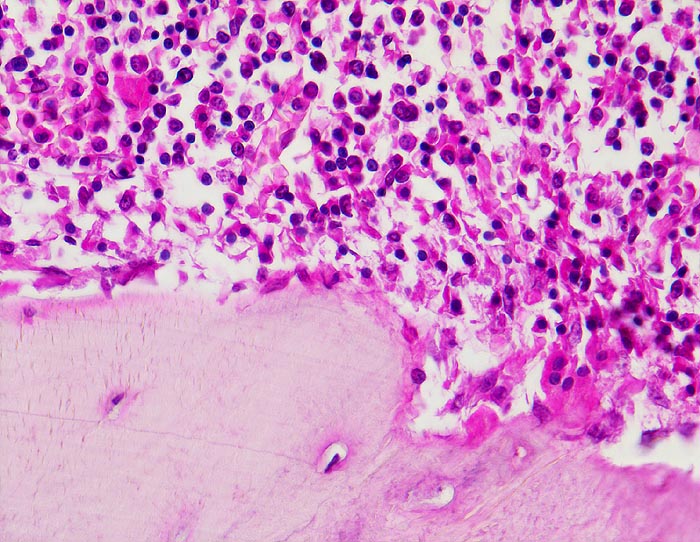

Normale Spongiosa

Normalbefund

Knochen, Wirbelsäule

Knochen, Knorpel, Gelenke

Normale Spongiosa mit

Osteoblasten an der Bälkchenoberfläche und blutbildendem Mark. Bei der mehrkernigen Riesenzelle rechts unten im Bild handelt es sich um einen

Osteoklasten.

Histologie

200